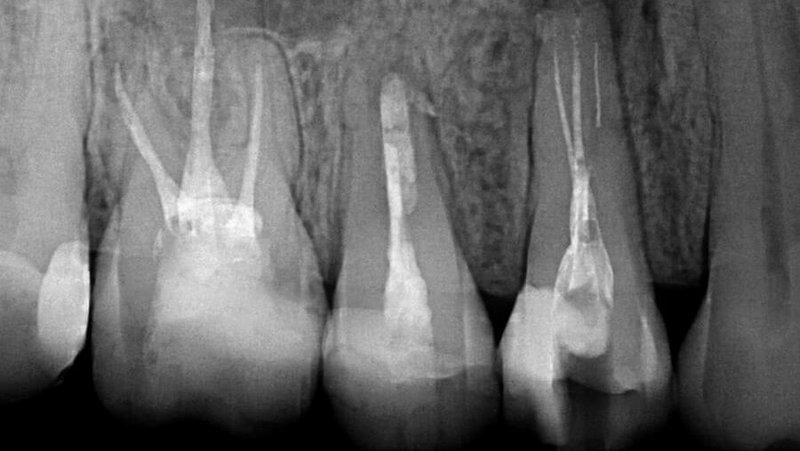

Ausgangslage Zahn 14: Separiertes Feilenfragment und Medikation in situ